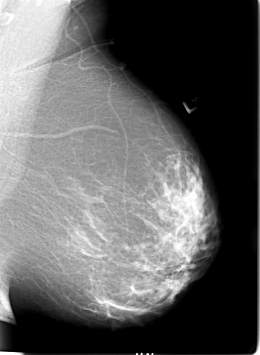

B_3020_1.LEFT_CC

LEFT_CC LINES 5672 PIXELS_PER_LINE 3976 BITS_PER_PIXEL 12 RESOLUTION 50 NON_OVERLAY